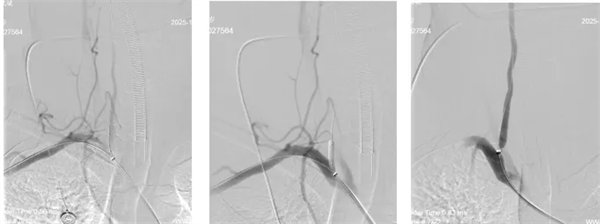

術(shù)中,介入團(tuán)隊(duì)精準(zhǔn)定位血管閉塞部位,通過(guò)微導(dǎo)絲“探路”聯(lián)合球囊擴(kuò)張技術(shù)開(kāi)通右側(cè)椎動(dòng)脈開(kāi)口,造影椎開(kāi)口殘余狹窄60%。基底動(dòng)脈血栓形成,基底動(dòng)脈管腔狹窄55%,基底動(dòng)脈尖堵塞,右側(cè)大腦后動(dòng)脈及小腦上動(dòng)脈未見(jiàn)顯影,左側(cè)大腦后動(dòng)脈P3以遠(yuǎn)閉塞。

席聰準(zhǔn)確鎖定患者基底動(dòng)脈處血栓,采用抽吸取栓技術(shù)快速開(kāi)通血管,成功取出堵塞部位2cm的血栓。再次造影示:右側(cè)大腦后及雙側(cè)小腦上動(dòng)脈再通,右側(cè)大腦后動(dòng)脈P3段以遠(yuǎn)閉塞,考慮慢性閉塞,推注替羅非班,血流明顯加快。隨后采用支架植入術(shù)開(kāi)通右側(cè)椎動(dòng)脈開(kāi)口處,術(shù)中影像顯示:支架貼壁良好,無(wú)明顯殘余狹窄,顱內(nèi)血管顯影良好。